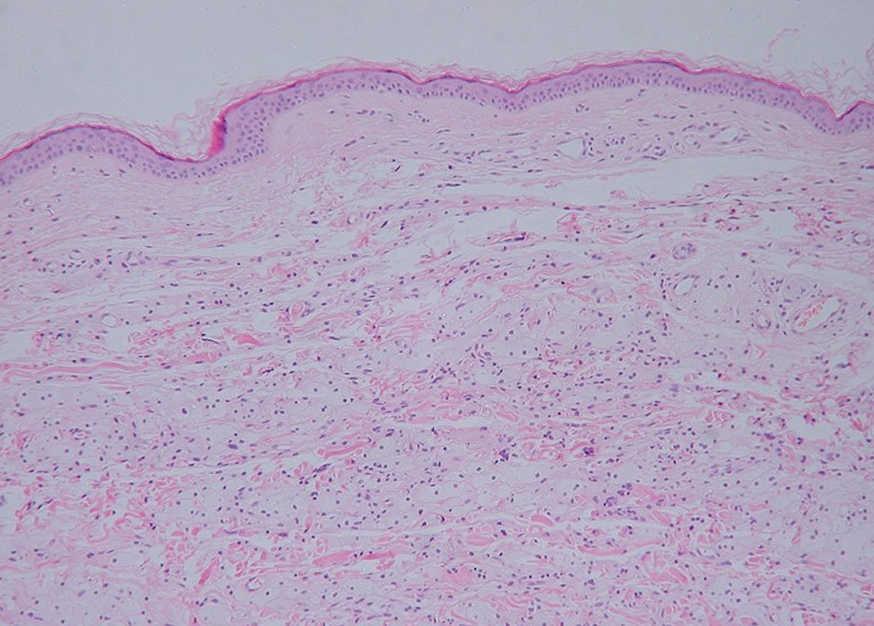

Fig. 4.--Infiltrado difuso en dermis superficial y media de células histiocitarias espumosas. No se observan linfocitos atípicos. (Hematoxilina-eosina, x20.)

Histológicamente se caracterizan por la presencia de un infiltrado en la dermis de células histiocitarias espumosas. Este infiltrado es variable, pudiendo verse desde células espumosas de forma aislada, a nidos celulares distribuidos difusamente por la dermis e incluso verdaderas lesiones xantogranulomatosas. En raras ocasiones pueden verse células gigantes de Touton o de cuerpo extraño. Junto a las células histiocitarias puede haber un infiltrado inflamatorio mixto con leucocitos y linfocitos en grado variable 3,4,7. Las células se tiñen con CD68 pero son negativas para CD1 y S-100 4,5.